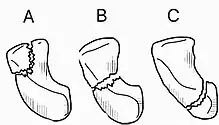

Fractures of scaphoid can occur either with direct axial compression or with hyperextension of the wrist, such as a fall on the palm on an outstretched hand. Using the Herbert classification system, there are three main types of scaphoid fractures. 10%-20% of fractures are at the proximal pole, 60%-80% are at the waist (middle), and the remainder occur at the distal pole.[4][7][8]

Treatment of scaphoid fractures is guided by the location in the bone of the fracture (proximal, waist, distal), displacement (or instability) of the fracture, and patient tolerance for cast immobilization.